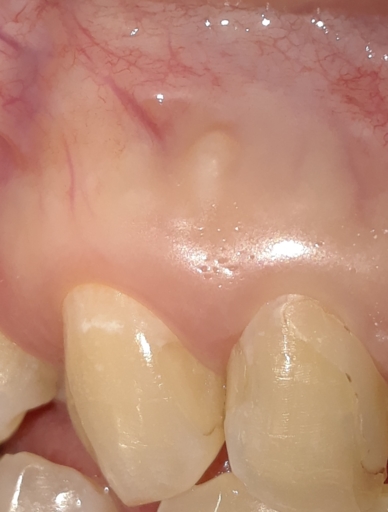

If My Front Tooth can be Salvaged.

Hi,I reinjured one of my front teeth that was previously injured after a fall and was pushed back in my mouth 1 yr ago. I had it positioned back into place, got a root canal done and had splinter over it. But 2 weeks ago I reinjured the tooth and it...